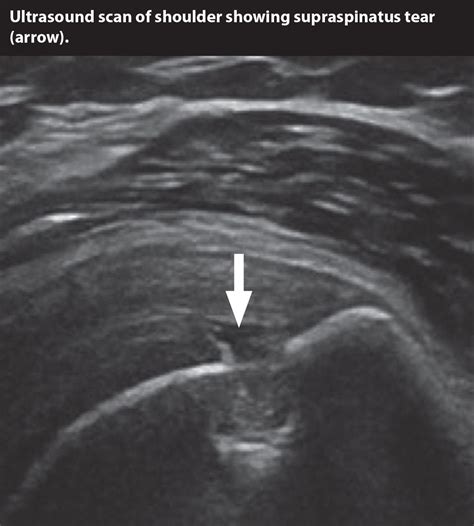

• Tendinopathy: Identifying thickening, tears, or calcifications within the tendon.

• Muscle Injuries: Visualizing strains, ruptures, or intramuscular hematomas.

• Ligament Tears: Assessing the integrity of superficial ligaments like the MCL or ATFL.